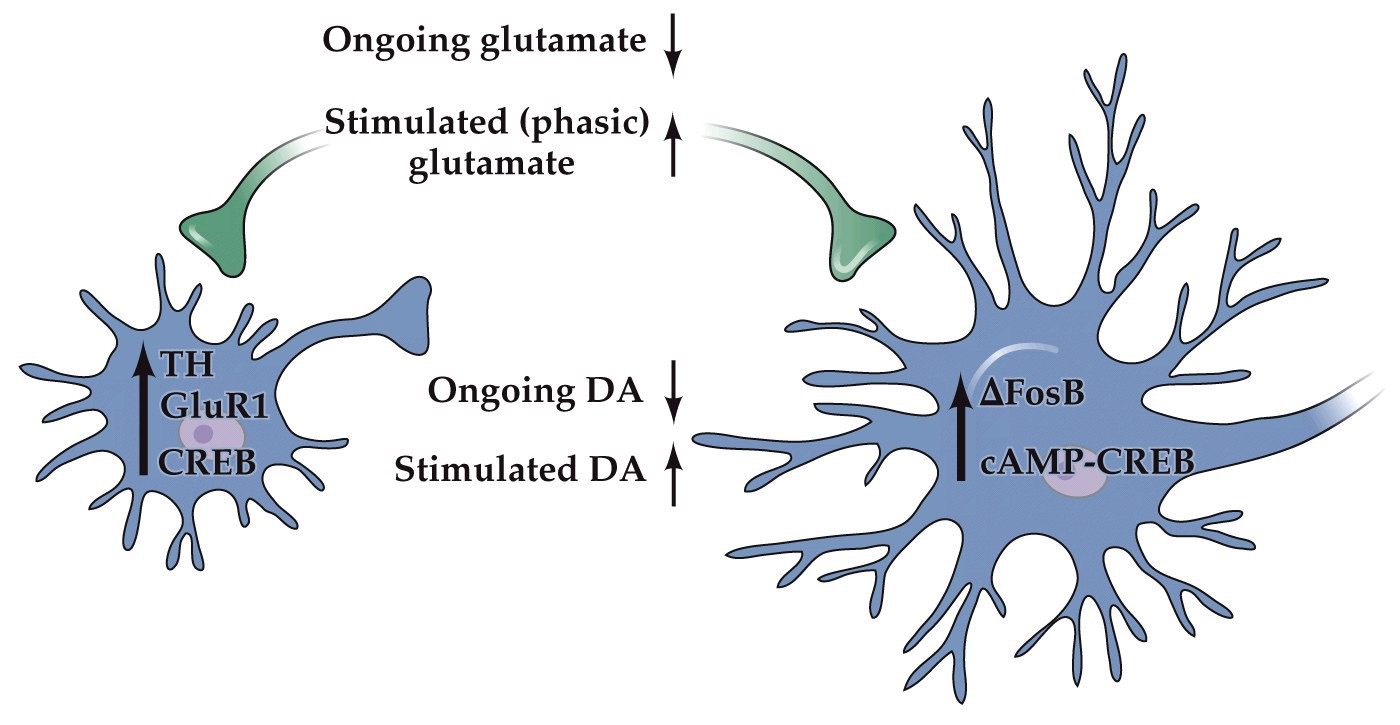

Substances of abuse affect dopamine projections from the VTA to the nucleus accumbens

Note:

Exposure to drugs of abuse causes long-lasting enhancement of excitatory input to VTA dopamine neurons, increasing AMPA/NMDA receptor ratio at these synapses.

Specifically, studies in primates and rodents have shown that many VTA dopamine neurons encode reward prediction errors. This error signal is hypothesized to direct synaptic plasticity in target neurons in the nucleus accumbens and prefrontal cortex for reinforcement-based learning. If VTA dopamine neurons signal a reward, the action or behavior that immediately preceded the reward is reinforced through dopamine modulation of downstream circuits (see Figure 10–44). Drugs of abuse bypass natural signals that activate these dopamine neurons, thus dissociating the reward system from its natural stimuli. Specifically, by increasing dopamine concentration at dopamine neurons’ presynaptic terminals, drug consumption mimics dopamine neuron activation; this reinforces the preceding actions, include drug consumption itself. Thus, addictive drugs hijack the brain’s reward system and exploit mechanisms that otherwise regulate learning and motivational

long-term changes addicts:

- Decreases in CREB transcription factor in NAc (and extended amygdala)

- Decreases in metabolism in orbito frontal cortex (OFC)

- Decreases in dopamine D2 receptor binding

Addictive substances hijack the brain’s reward system by enhancing the action of VTA dopamine neurons

- Addiction: compulsive subtance intake despite long-term negative consequences

- All drugs of abuse increase dopamine concentration at the output targets of the ventral tegmental area

- Nucleus accumbens– processes reward information

- Prefrontal cortex– goal selection and decision making